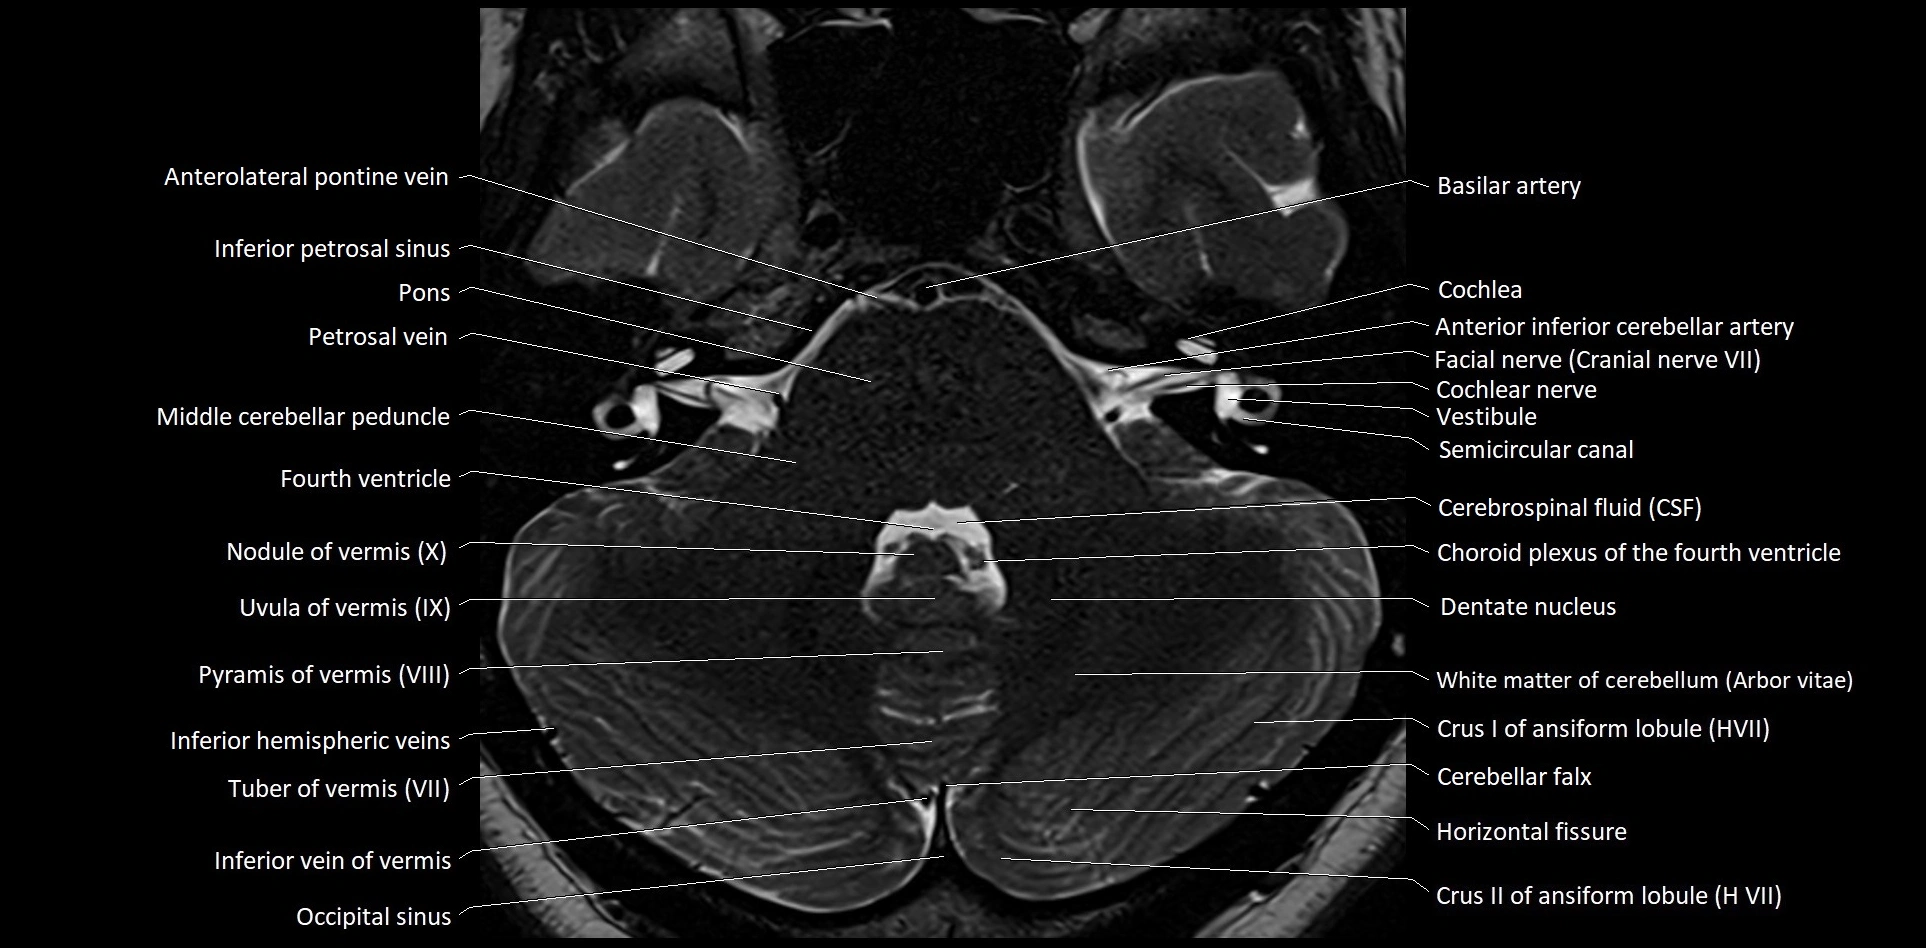

- Anterolateral pontine vein

- Cochlea

- Cochlear nerve (Cranial nerve VIII)

- Crus I of ansiform lobule of cerebellum

- Crus II of ansiform lobule of cerebellum

- Dentate nucleus

- Facial Nerve (Cranial nerve VII)

- Horizontal fissure (cerebellum)

- Inferior hemispheric veins of the cerebellum

- Inferior petrosal sinus

- Inferior vein of vermis

- Middle cerebellar peduncle

- Nodule of vermis

- Nodule of vermis (X)

- Occipital sinus

- Petrosal vein

- Pyramid of vermis (VIII)

- Pyramis of vermis

- Semicircular Canals

- Tuber of vermis (VII)

- Uvula of vermis

- Uvula of vermis (IX)

- Vestibule

- Vestibulocochlear nerve (Cranial nerve VIII)

- White matter of cerebellum (Arbor vitae)